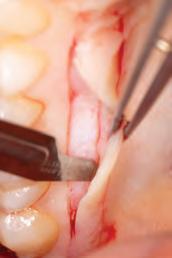

In general, most clinical situations that present with gingival recession also involve a deficiency of keratinized attached gingiva, which requires mucogingival surgery.35 The periodontal plastic surgery procedures available for the treatment and correction of gingival recession include free gingival autografts, subepithelial connective tissue grafts, coronally positioned flaps, guided tissue regeneration, and acellular matrix grafts.36–41 These soft tissue grafts are indicated for the restoration of noncarious and carious cervical radicular lesions and for previously placed restorations associated with gingival recession. Recent advances in periodontal plastic surgery procedures have stimulated reassessment of the envelope technique and its modified version, the tunnel technique, for root coverage of single and multiple adjacent gingival recessions.36,42,43

The envelope technique originated in 1985 for single gingival recession defects.36,44 This procedure involved vertical incisions on either side of a tunnel preparation that

enabled placement of a subepithelial connective tissue graft within the tunnel to cover the gingival recession. The modified microsurgical technique eliminates the vertical incisions and allows the construction of a tunnel under the gingival tissue by means of a sulcular incision beyond the mucogingival line without raising a flap. This alteration of technique by using newly developed microsurgical instruments allows an undermining split-flap preparation of the facial tissues, ensuring improved blood supply, early wound healing, predictable root coverage, and esthetic postoperative results.45–53 This modified microsurgical approach simplifies the technique and allows for the treatment of multiple adjacent gingival recession defects in one surgical visit.